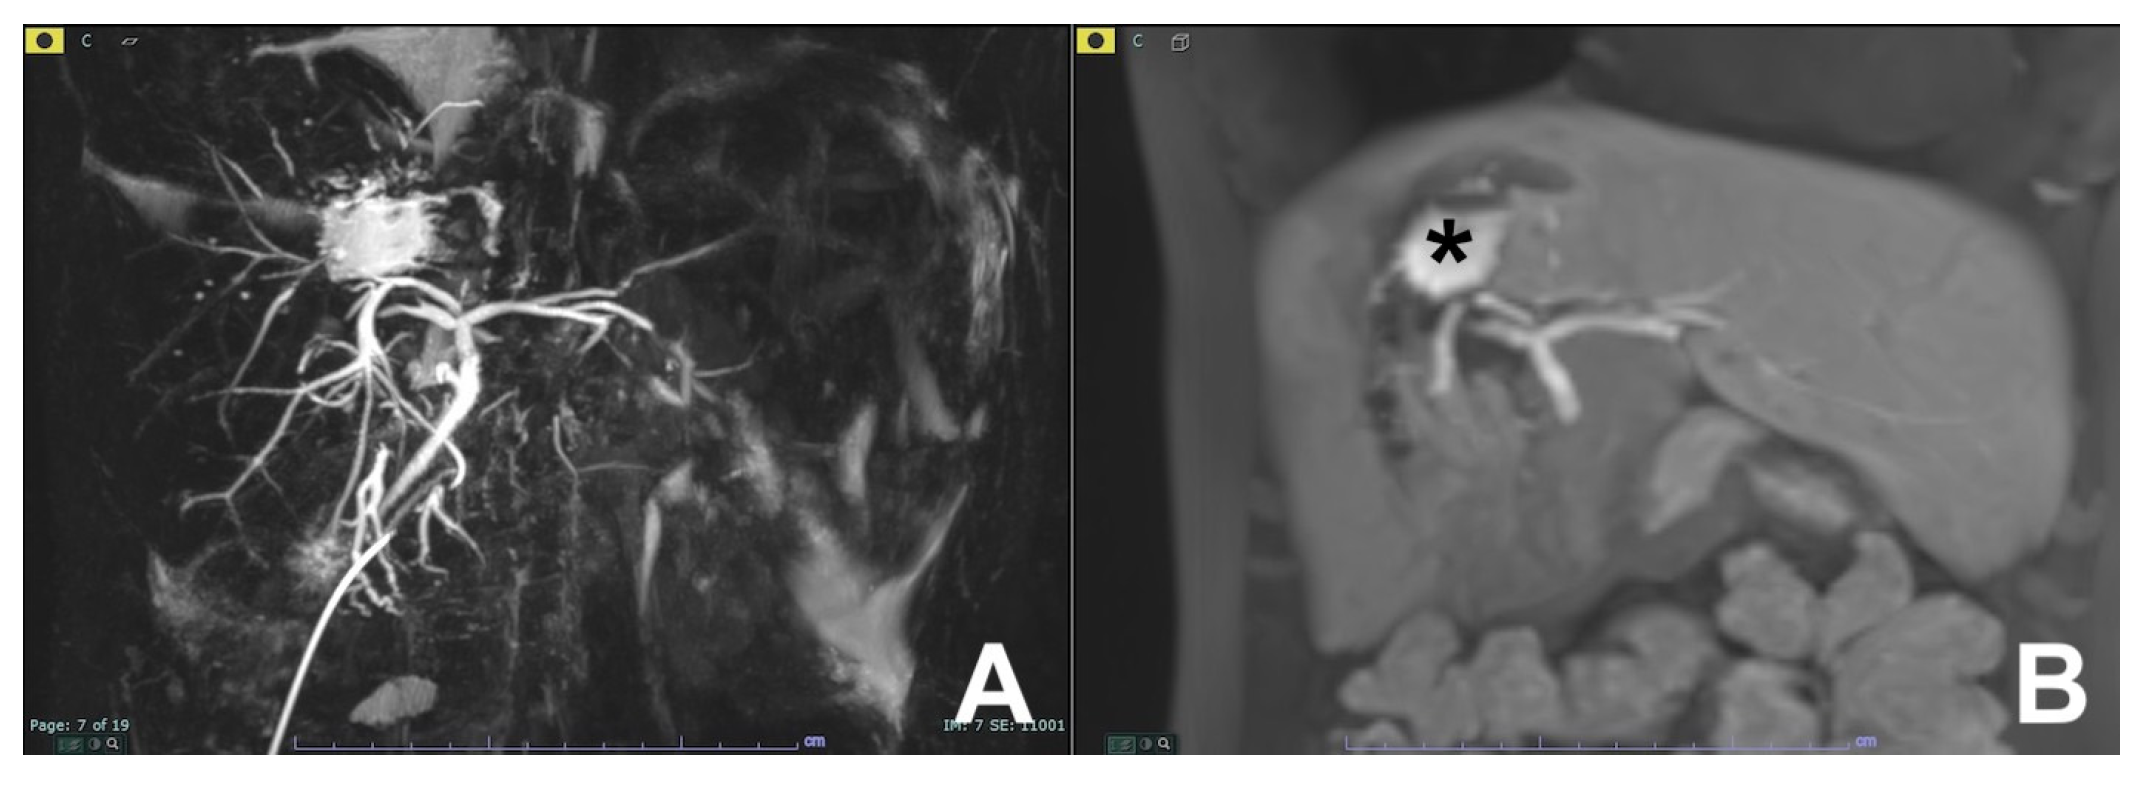

| Differential diagnosis pancreatic cancer (PC) from mass forming pancreatitis (e.g., paraduodenal pancreatitis-PDP, autoimmune pancreatitis-AIP) | HASTE T2 | AXIAL | -- | Anatomy and liquids analysis |

| Indications: The use of multiparametric imaging (DWI, contrast enhanced) allows one to differentiate with substantial accuracy a mass forming pancreatis from a pancreatic carcinoma. | HASTE T2 | CORONAL | -- | Anatomy and liquids analysis |

| GRE T1 FS | AXIAL | -- | Pancreatic parenchima assessment | |

| DWI b 0–50–400–800 | AXIAL | -- | Restricted diffusion most likely to be PC or AIP | |

| GRE T1 3D DYNAMIC | AXIAL | Pre- 25″–70″–180″ | PC is most likely hypovascular; mass forming pancreatitis usually shows delayed homogeneous enhancement | |

| MRCP 3D/2D | OBLIQUE CORONAL | Anatomy of wirsung duct | ||

| MRCP 2D with secretin | OBLIQUE CORONAL | For the differential diagnosis of pancreatic duct stenosis (“duct penetrating sign”) | ||